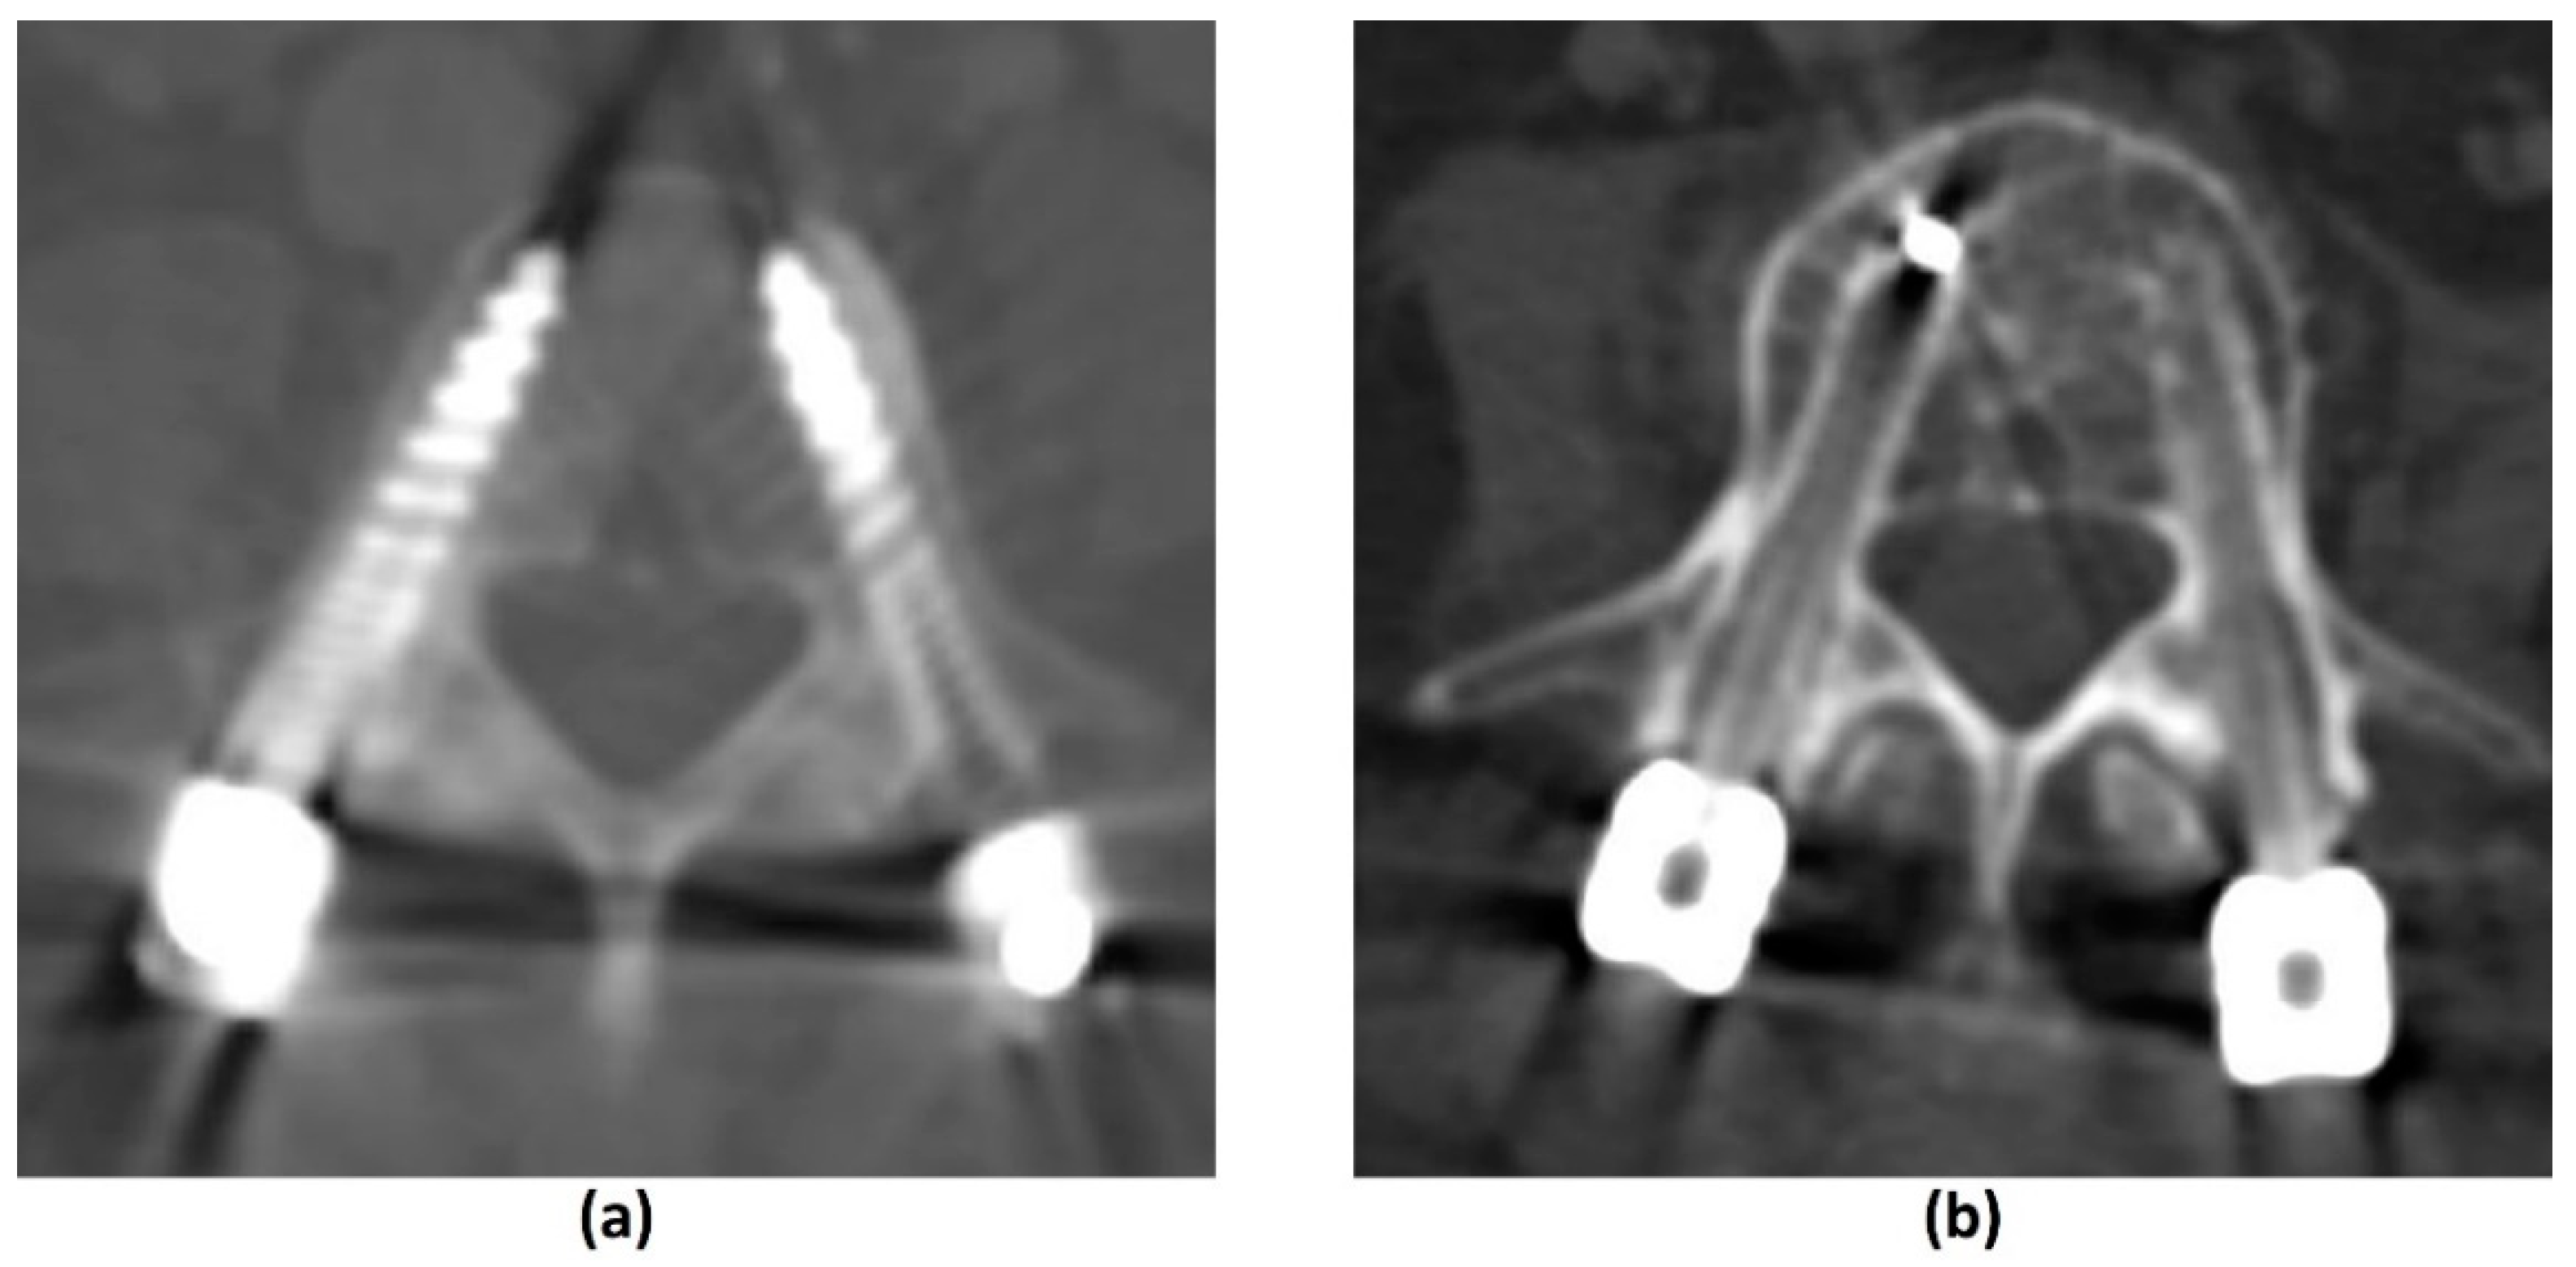

3.4.1. Challenges of CT: Metal-Related Artifacts

3.4.2. Photon-Counting CT